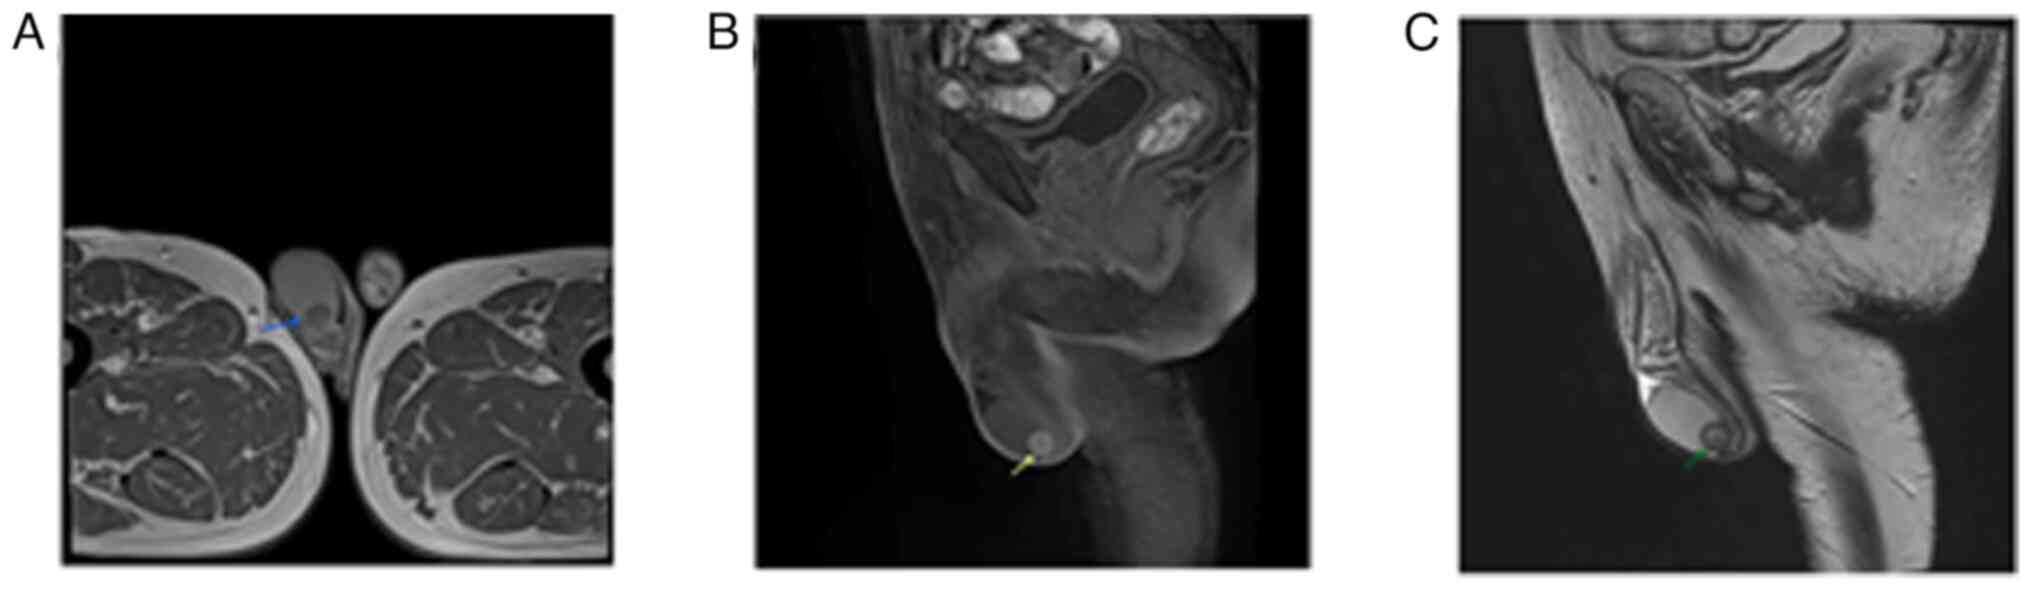

Cholesterol granulomas (ChGs) are benign fibro‑granulomatous lesions that develop following trauma and inflammation. The most common sites of presentation are the middle ear, paranasal sinuses and petrous apex; however, they can present in any area of the body where cholesterol deposition can occur. The present study describes the case of a 62‑year‑old male who presented with a painless right scrotal mass that had been there for the past 6 years. Upon a physical examination, a hard non‑tender mass at the lower pole of the right testis with normal overlying scrotal skin was detected. Blood analyses revealed normal levels of tumor markers (β‑human chorionic gonadotropin, alpha‑fetoprotein and lactate dehydrogenase) and a normal lipid profile. A right scrotal color Doppler ultrasound revealed a well‑defined hypoechoic 13x14 mm lower pole testicular mass. Scrotal magnetic resonance imaging revealed a well‑defined nodule (13x11x12 mm) at the lower pole of the right testis near the epididymis. Under spinal anesthesia, via inguinal incision, a right partial orchiectomy was performed. The post‑operative period was uneventful. The results of the histopathological examination were consistent with testicular ChG. ChG of the testis is extremely rare, and only one other case has been recorded in the literature to date, at least to the best of our knowledge. Differentiating between ChGs of the testis and testicular tumors before surgery can be relatively challenging. This should be regarded as a differential diagnosis in cases of testicular masses.